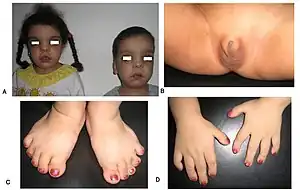

Robinow noted the resemblance of affected patients' faces to that of a fetus, using the term "fetal facies" to describe the appearance of a small face and widely spaced eyes.[1] Clinical features also may include a short, upturned nose, a prominent forehead, and a flat nasal bridge. The upper lip may be "tented",[1] exposing dental crowding, "tongue tie", or gum hypertrophy.

Though the eyes do not protrude, abnormalities in the lower eyelid may give that impression. Surgery may be necessary if the eyes cannot close fully. In addition, the ears may be set low on the head or have a deformed pinna.[1]

Patients suffer from dwarfism, short lower arms, small feet, and small hands. Fingers and toes may also be abnormally short and laterally or medially bent. The thumb may be displaced and some patients, notably in Turkey, experience ectrodactyly.[1] All patients often suffer from vertebral segmentation abnormalities. Those with the dominant variant have, at most, a single butterfly vertebra.[2] Those with the recessive form, however, may suffer from hemivertebrae, vertebral fusion, and rib anomalies. Some cases resemble Jarcho-Levin syndrome or spondylocostal dysostosis.[1]

Genital defects characteristically seen in males include a micropenis with a normally developed scrotum and testes. Sometimes, testicles may be undescended, or the patient may suffer from hypospadias.[2] Female genital defects may include a reduced size clitoris and underdeveloped labia minora. Infrequently, the labia majora may also be underdeveloped.[2] Some research has shown that females may experience vaginal atresia or haematocolpos.[3]